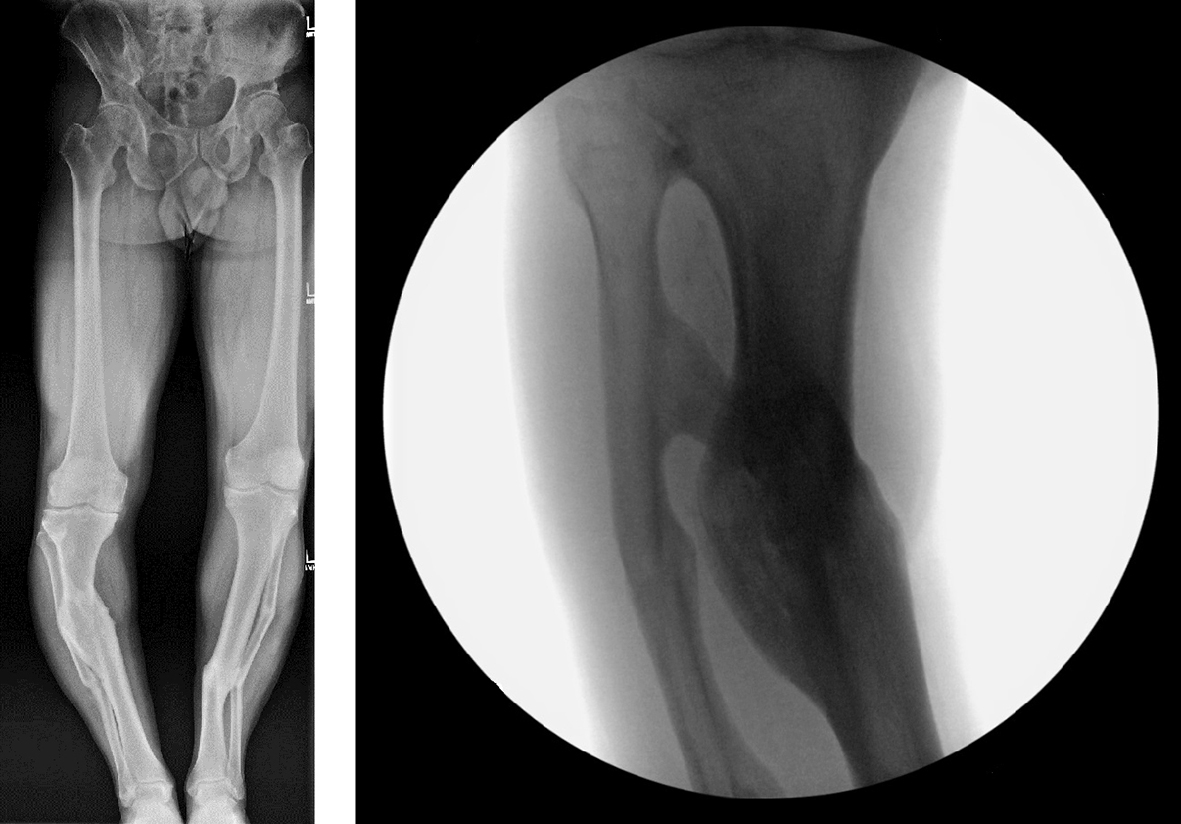

A 54-year-old man suffered bilateral tibial fractures 20 years earlier, both treated in a cast. He now experiences pain in the medial right knee. Images taken showed that both legs had substantial malunion, but the right knee caused pain because it was out of mechanical axis (Fig 11). The patient was successfully treated with the MAXFRAME system (Figs 12 to 15).